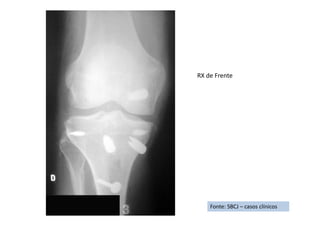

RX de Frente

Fonte: SBCJ – casos clínicos